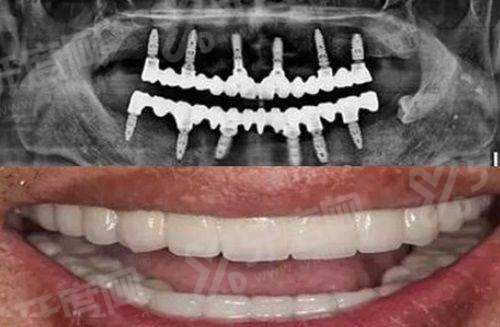

1、数字化种植技术:引进3D导航种植技术,通过CBCT三维影像精细扫描患者口腔结构,术前模拟种植方案,术中使用导板引导种植体植入,提高种植精度和成功几率,减少手术创伤,缩短术后修复时间,尤其适合牙槽骨条件复杂的患者。

黄石湖科中山口腔半口即刻负重种植牙价格:2.5万元起

黄石湖科中山口腔全口微创种植牙价格:4万元起